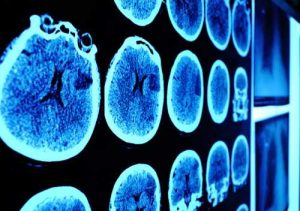

Parkinson’s disease is a progressive degenerative disorder of the central nervous system that affects the motor system of those affected. Nearly 60,000 Americans are diagnosed with Parkinson’s disease each year, with thousands of cases going undetected. Common symptoms of Parkinson’s include tremors, stiffness, and rigidity. This causes patients to have slow movements throughout their lives, ...click here to read more